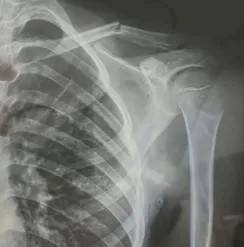

10月30日,内蒙古自治区赤峰市宁城县苏木皋小学一学生家长贾女士给记者打来电话,介绍了孩子被打的原因三角货币对冲指标。贾女士称,放学通道的墙上有一个电灯的开关,好多孩子放学时都随手去拨弄开关。出于安全考虑,学校和老师都禁止孩子拨弄开关。23日放学时,他儿子和另一个同学调皮,再去拨弄了那个开关,被正在值班的另一个班的班主任发现,把她儿子打了,且打骨折了。

图片由报料者提供